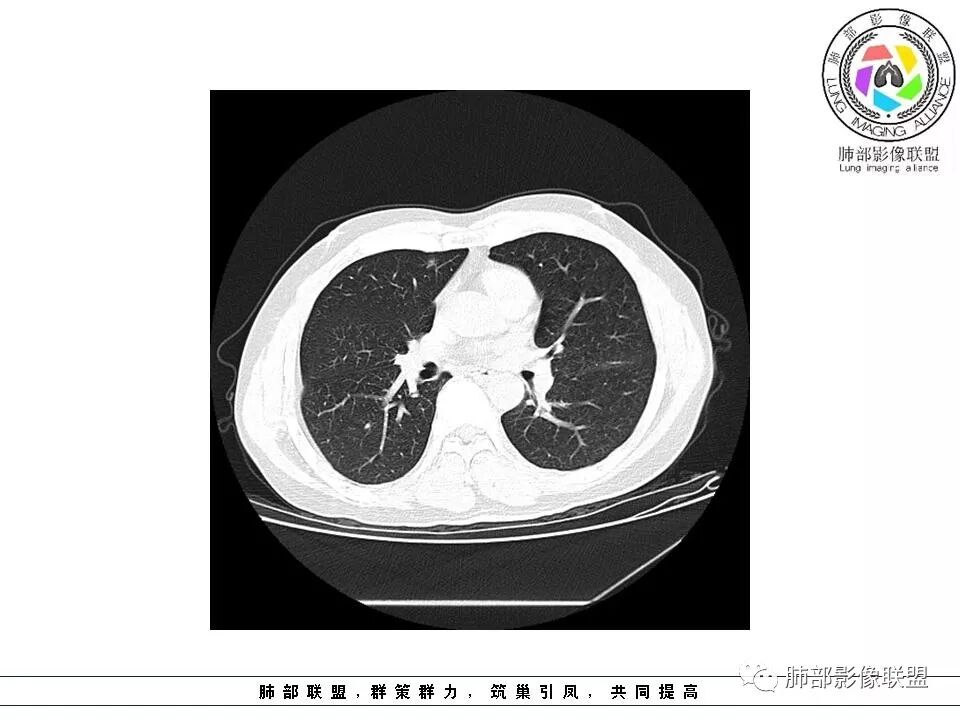

群内讨论

杨泽锋:很难通过一次CT检查来判断小结节的性质炎性结节可能大理由:病灶很小但是很密实毛刺比较长百事可乐:右肺中叶内侧段实性小结节,毛刺、分叶,胸膜牵拉。考虑MIA。李:实性结节,形态不规则,考虑炎性肉芽肿紫气东来:右肺中叶实性结节,毛刺分叶,考虑恶性。穿越七海的风:右肺上叶近胸膜下小结节,实性度较高,肺内淋巴结吧,可随访观察张帅:晨读,右肺上叶前段小结节病变,病灶内可见细支气管穿过,局部血管略增粗,病灶边界清,可见软毛刺,3月胸CT较2月貌似密度减低,毛刺变小,考虑良性病变,炎性病变?春秋:患者51男性,右上叶前段结节,形态不规整,明显分叶,前后变化不明显,考虑恶性!Yiren  Sishui(厶水伊人):小结节,密度较实,有多条线状影,胸膜下分布,肺内淋巴结?炎性肉芽肿?建议随访。东哥:晨读:右肺上叶小结节,不规则,可见分叶,整体收缩,两次CT变化不明显,先考虑良性可能我心飞翔:右上肺实性结节,长毛刺,考虑良性病变王秀仙:晨读:右肺上叶结节,边缘毛刺,一个月后,病灶略有增大,边缘小叶间隔阻挡,考虑腺癌。Shelia🌞:晨读,右肺上叶前段胸膜下小结节,形态不规则,以平直收缩为主,可见u型凹陷,长毛刺,1月复查感觉变化不大,考虑炎性病变,建议继续随访复查除外腺癌一切∮随缘:晨读病例:     右肺上叶前段可见一不规则结节,边缘可见分叶,毛刺,清晰的GGO,近端牵拉血管树,未见明显支气管截断,中年男性,体检发现,综合考虑微浸润腺癌,待排炎性肉芽肿,建议短期随访。

Ao..葉偲雨!👑:右肺中叶内侧段小结节,边缘毛刺,部分层面平直,第二次复查有凹陷,密度似乎比之前淡泊一点(肿瘤的生长周期一个月一般不会有太多变化),大小范围基本稳定,LU-Rads 4a类,炎性结节可能,建议3个月后复查或pet

南边分析

南边:51岁男性,体检发现右肺结节这个年龄段的男性,啥都可以发生,也属于肺癌的高危人群南边:首先是实性还是GGO?好像实性吧